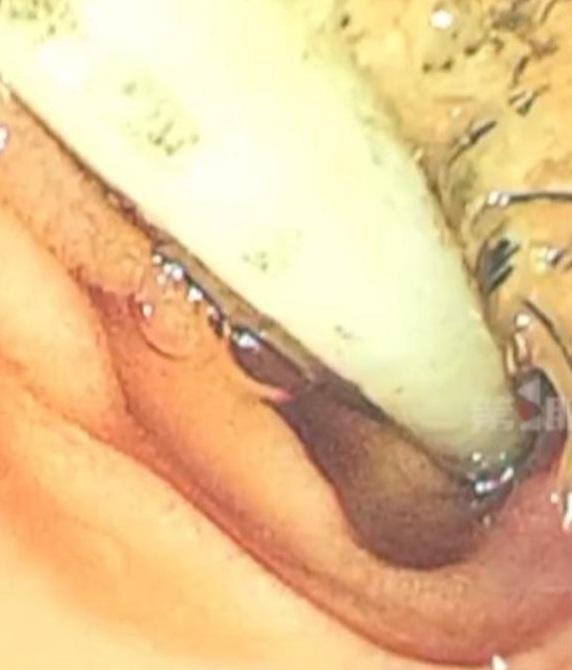

醫生動手術,替楊姓男子取出52年前的兒童牙刷。(互聯網)

內媒《縱覽新聞》等報道,楊姓男子近日因胸痛難耐,前往醫院接受檢查。醫生進行胃鏡和電腦掃描檢查後,發現他腹部竟有一支兒童塑膠牙刷。醫生指,在病人的十二指腸球部彎曲處發現藏著一支牙刷,所幸牙刷長期沒移動,所以腸壁未受嚴重傷害。醫生團隊隨即進行手術,替病人取出牙刷。